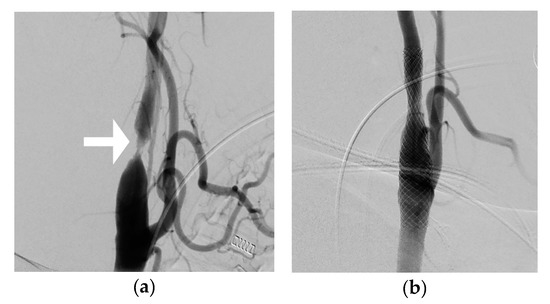

2. Materials and Methods

3. Results